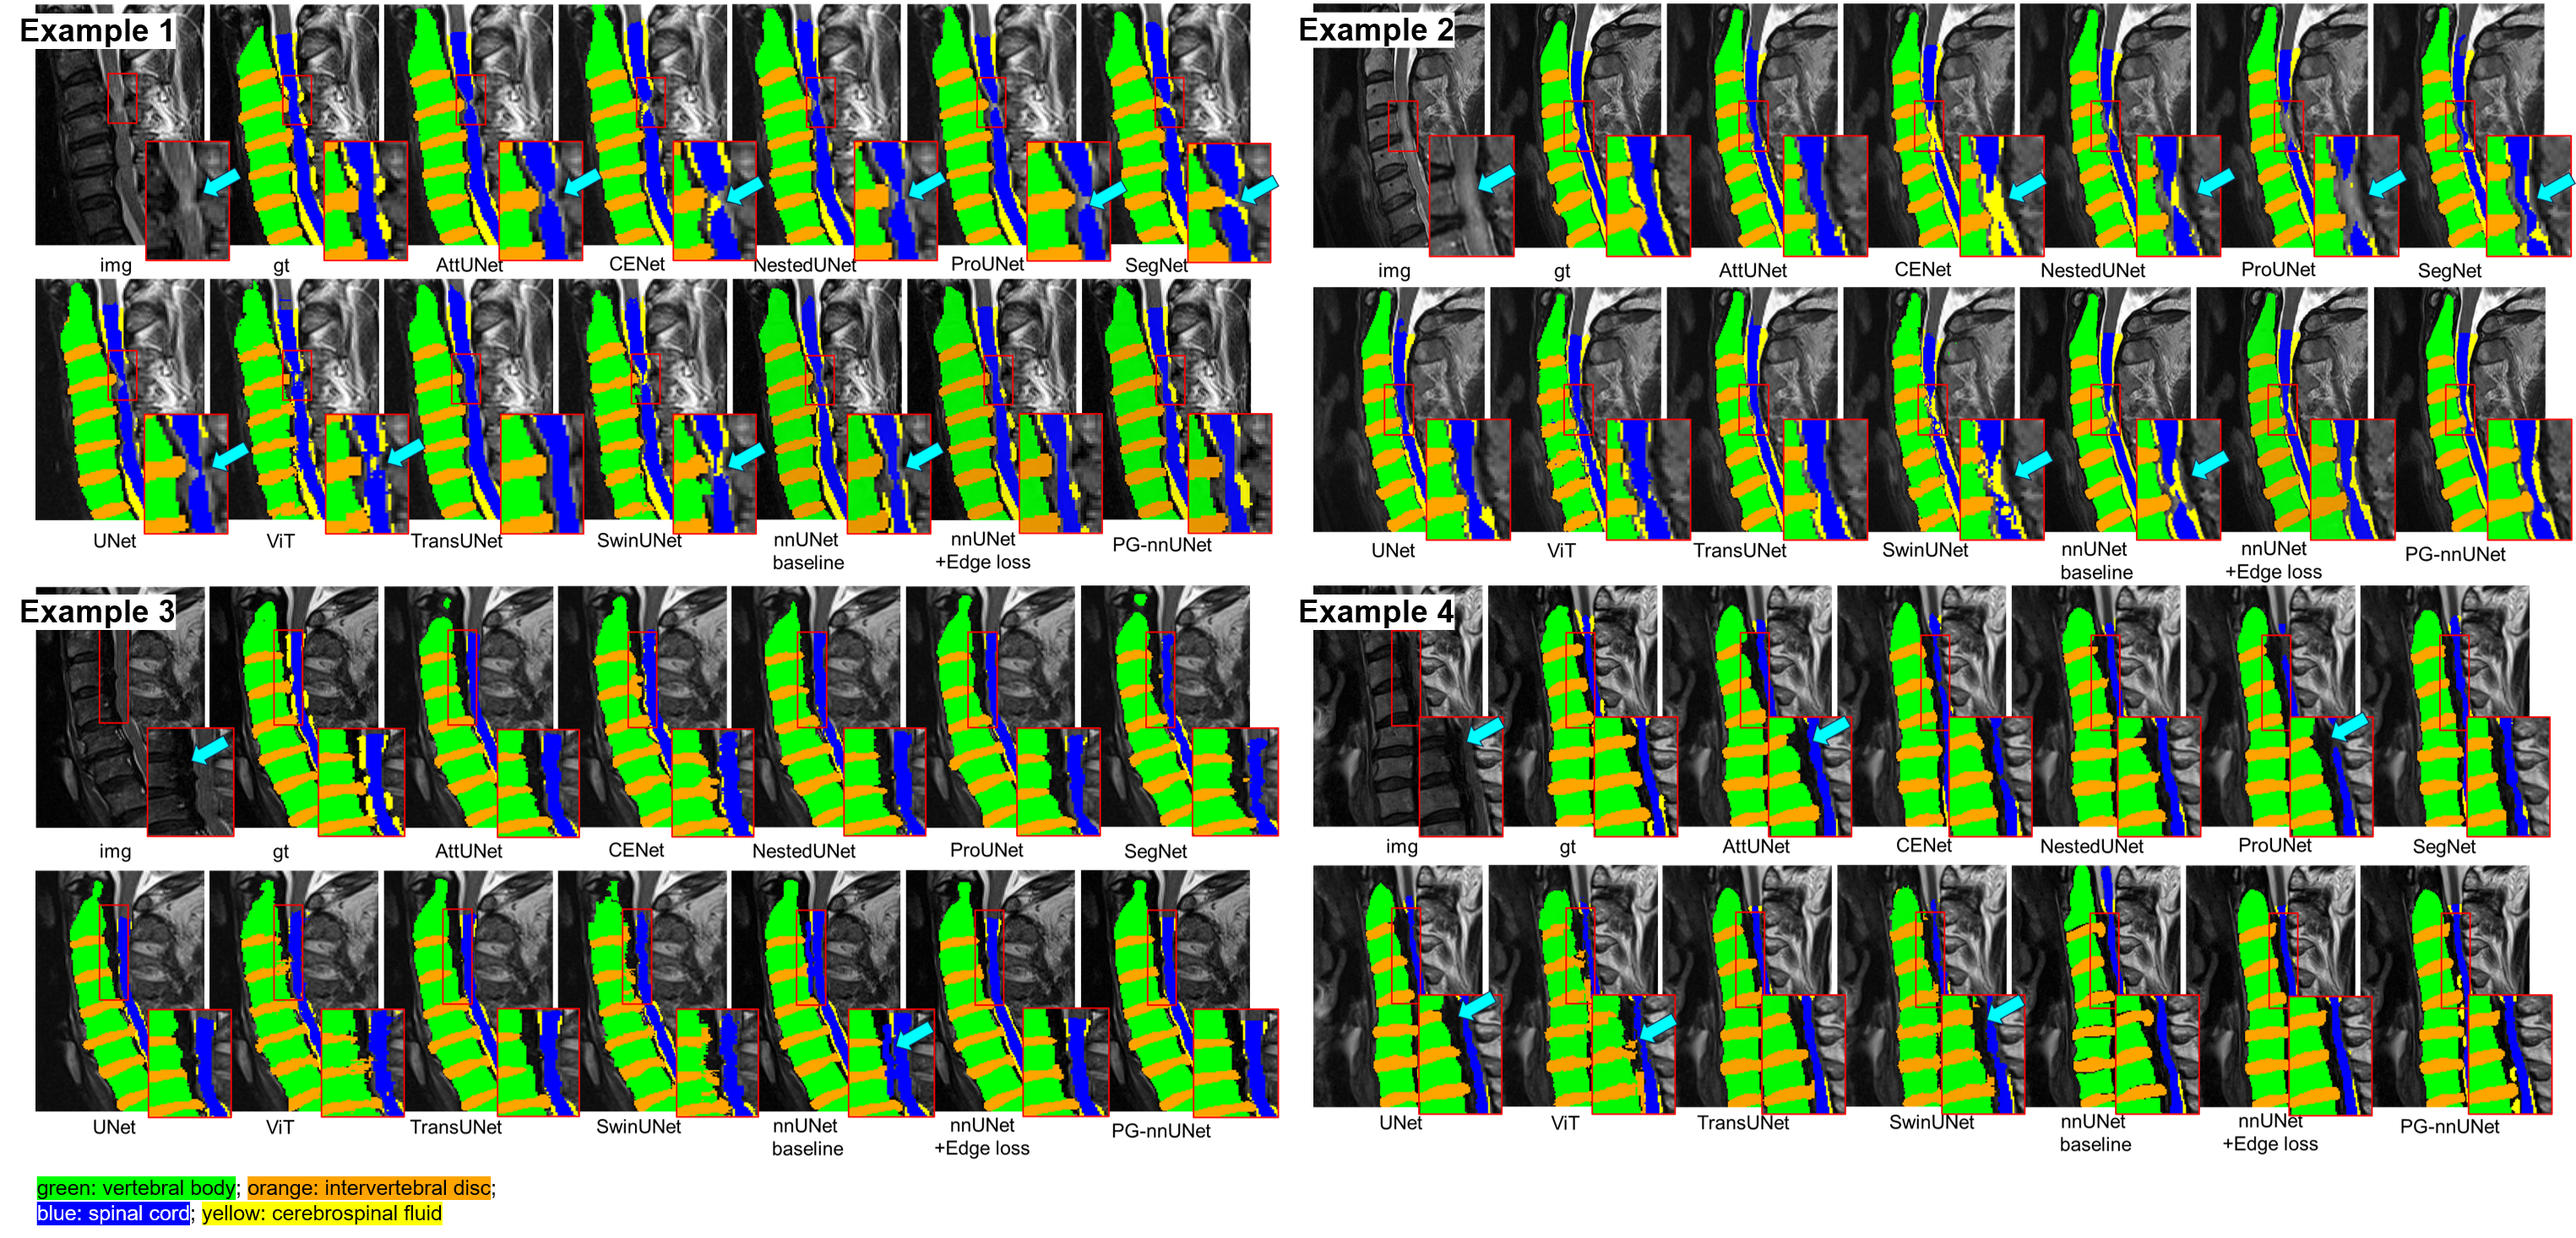

5.2 Visual Comparison of Segmentation Results

Figure 6 visualizes the segmentation predictions for several cases across different models. Example 1 and 2 highlight cases with T2 hyperintensity in the spinal cord (indicated by the red box), which is particularly challenging to predict accurately. Models such as CENet, NestedUNet, SwinUNet, and the nnUNet baseline failed to distinguish this region from CSF, and ProUNet incorrectly classified it as background. In contrast, nnUNet combined with edge loss and our proposed PG-nnUNet were able to accurately segment the region, thereby preventing errors in subsequent diagnoses. Example 3 and 4 show cases with ossification of the posterior longitudinal ligament (OPLL) (red box). Many models failed to segment the ossified region accurately (marked by blue arrows), likely due to differences in intensity compared to adjacent tissues. The nnUNet baseline even misclassified the ossification as part of the spinal cord in Example 3. However, our proposed PG-nnUNet performed well, effectively detecting these pathological regions and avoiding segmentation errors.

Refer to caption

Figure 6: Examples of cervical spine segmentation results and comparisons across different models. The red boxes indicate pathological areas, such as T2 hyperintensity in the spinal cord and ossification of the posterior longitudinal ligament (OPLL).